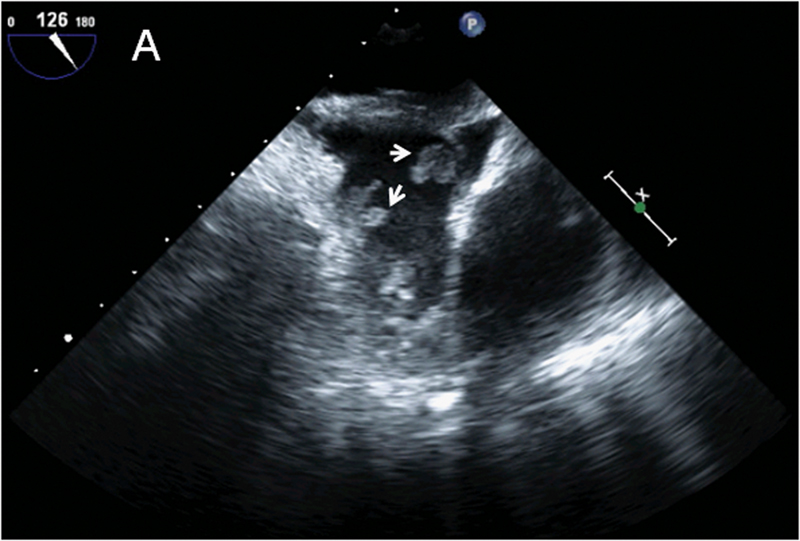

فحوصات تشخيصية لبعض امراض القلب والشرايين التاجية